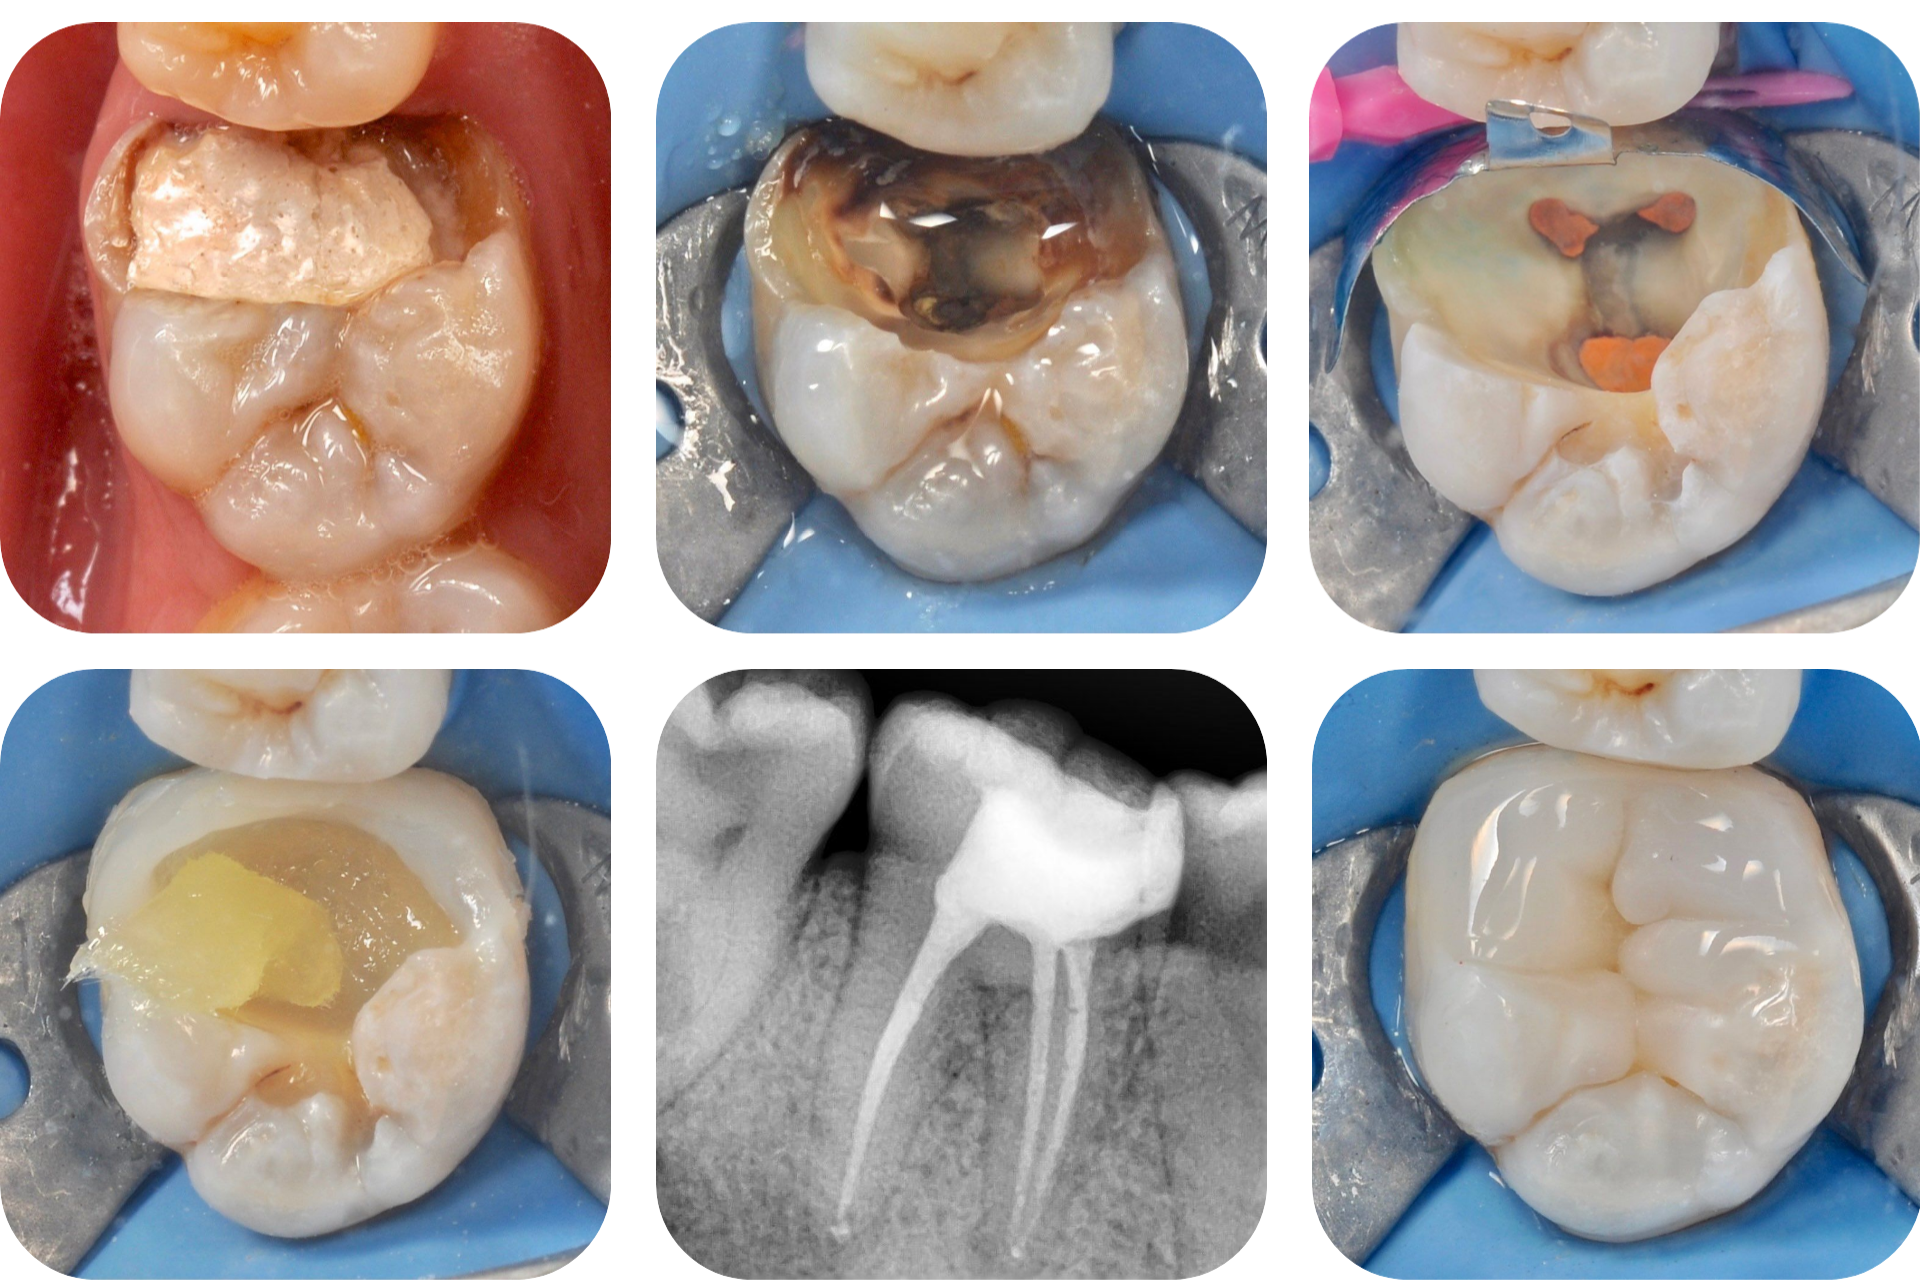

Пульпит и периодонтит

Пульпит и периодонтит носят воспалительный характер и являются следствием невылеченного кариеса.

Этапы лечения:

1. Точное определение формы каналов.

Высокоточный рентген показывает форму каналов и область воспаления.

2. Тщательная обработка каналов.

Точное определение геометрии каналов и их качественная обработка.

3. Укрепление зуба стекловолокном.

Создаем прочную основу внутри зуба.

4. Устанавливаем коронку или фотополимерную пломбу на вылеченный зуб.

Защищаем зуб от внешней среды.